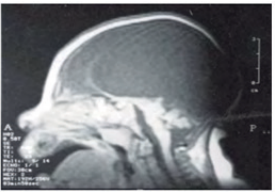

El caso clínico es un recién nacido de género femenino, hijo de padres jóvenes sanos, sin antecedentes de consanguinidad ni endogamia, ni de la patología en los familiares, producto de la primera gestación con un control de la gestación de forma irregular. La bebé nació por cesárea, con cráneo deprimido en su región superior, con piel y cabellos escasos, globos oculares protruidos con órbitas oculares orientadas hacia fuera y arriba, frente corta inclinada hacia atrás, hipertelorismo ocular, filtrum alargado, prognatismo mandibular, orejas de baja implantación mal formadas, cuello sumamente corto y piel ictérica (figura 1). Una tomografía axial computarizada (TAC) del sistema nervioso central (SNC) reporta “Anencefalia, hidrocefalia, cerebelo normal y tallo cerebral normal”. El reporte del TAC indica que hay cerebelo y tallo cerebral, pero no hemisferios cerebrales. La presencia de hidrocefalia significa que existe líquido ventricular en el espacio que deberían ocupar los hemisferios cerebrales. Por la presencia de restos de los hemisferios cerebrales, del tallo cerebral, del cráneo membranoso y de líquido ventricular se reporta en la historia el diagnóstico de hidra-meroanencefalia (figura 2). La niña evolucionó sin necesidad de la UCI, lo cual indica una función adecuada del tallo cerebral, y fue dada de alta con la recomendación del control pediátrico. No hay concordancia entre el diagnóstico emitido en la TAC y el correcto que debe realizarse. Al revisar estos casos en las bases de datos es raro encontrar el concepto de meroanencefalia, porque la gran mayoría de los artículos la siguen diagnosticando como anencefalia.